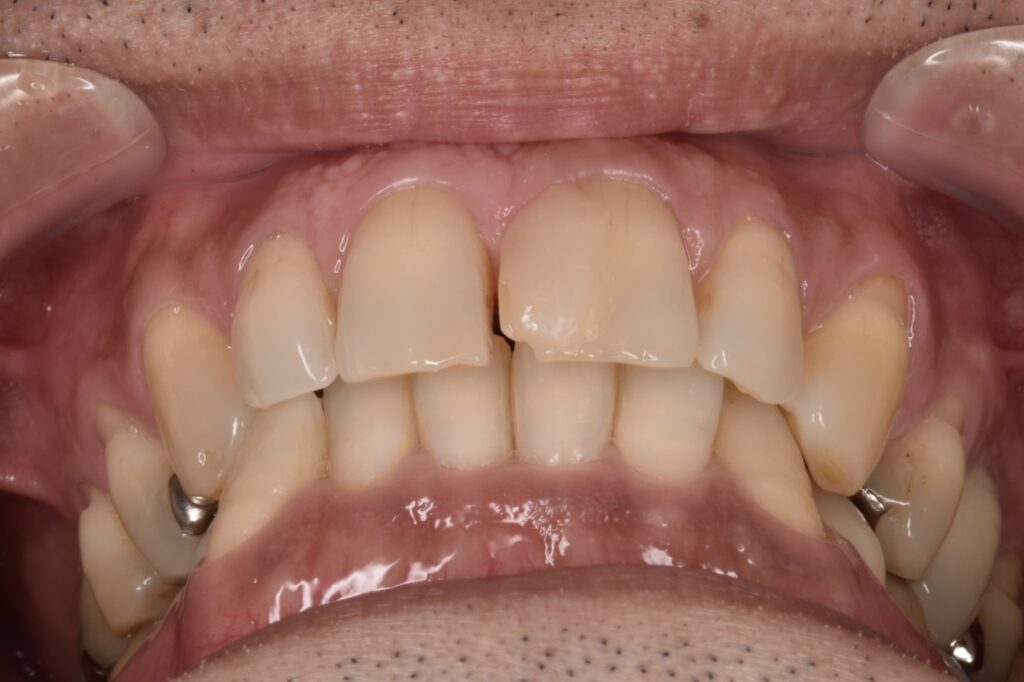

50代男性です。当院にご相談してくださる前に他院で前歯2本のダイレクトボンディング?を受けられたそうです。前歯2本の隙間は確かに白いレジンで埋められていましたが、本当に盛って作っただけのもので、違和感がかなり強かったそうです。

施術前

当院でタイレクトボンディング2歯のやりかえをご希望されて、2本でご契約してくださいました。他院のレジンは前日に取れたそうです。